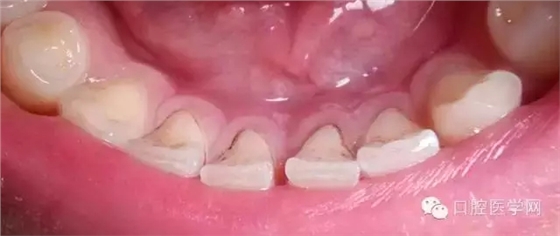

另一種則是牙齒出現(xiàn)了或深或淺的齲壞,從外面看就表現(xiàn)為一個(gè)黑點(diǎn),通常位于窩溝點(diǎn)隙(牙面上點(diǎn)狀或線狀凹陷)。齲齒的罪魁禍?zhǔn)资强谇恢械哪承┘?xì)菌,但它們破壞牙齒也是需要時(shí)間的,從初期的變色到最終形成齲洞,通常需要1年半到兩年。在此期間,我們多留心自己的牙齒,完全可能把齲壞扼殺在萌芽階段。如何才能及時(shí)發(fā)現(xiàn)這種隱匿的蛀牙呢?找位好牙醫(yī),半年檢查牙齒!

因此,平時(shí)應(yīng)注意自檢,觀察牙齒顏色、形狀、質(zhì)地的變化,還要每半年進(jìn)行全面的口腔檢查,如果有齲齒,就應(yīng)該早發(fā)現(xiàn)早治療。